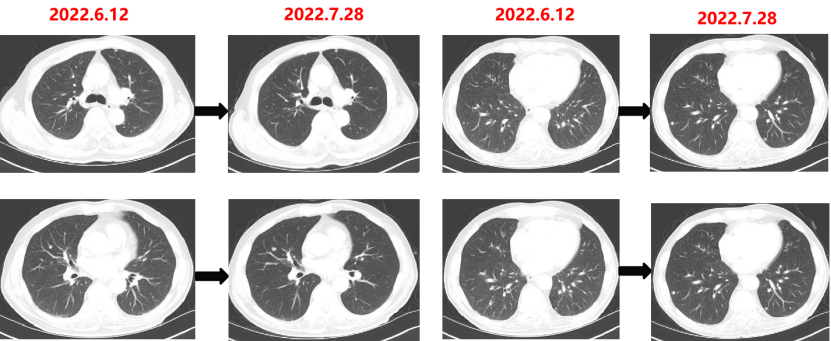

Q1 对于晚期转移性结直肠癌患者,目前,免疫治疗在新辅助治疗中的研究进展和临床应用如何? 结直肠癌是全球第三大肿瘤,转移性结直肠癌的5年生存率只有14%,治疗手段包括手术、化疗、放疗和靶向治疗等。免疫检查点抑制剂的出现也改写诊疗指南。大肠癌dMMR/MSI-H亚型约占所有病例的15%和mCRC病例的5%。由于dMMR/MSI-H的高突变率,肿瘤具有高免疫原性,使其能够激活免疫系统的抗肿瘤作用。 KEYNOTE-177这是一项三期国际开放标签随机对照研究,入选MSI-H/dMMR的IV期结直肠癌患者,比较帕博利珠单抗治疗(200 mg,每3周1次,最多35个周期)与在一线中使用或不使用抗VEGF或抗EGFR单克隆抗体的标准双药化疗,主要终点是PFS和OS。结果显示,帕博利珠单抗组患者的中位PFS时间为16.5个月 VS 8.2个月;3年PFS率分别为42% VS 11%,3年OS率分别为61% VS 50%。帕博利珠单抗组ORR为45.1%(20例完全缓解,49例部分缓解),化疗组为33.1%(6例完全缓解,45例部分缓解);帕博利珠单抗组83.5%的患者至少维持缓解了2年;在化疗组中,只有33.6%的患者缓解持续时间≥2年。KEYNOTE-177研究证实了帕博利珠单抗可以作为MSI-H或dMMR患者的一线标准治疗。 在2021版CSCO结直肠癌诊疗指南中,MSI-H结直肠癌姑息一至三线均推荐免疫治疗,其中帕博利珠单抗作为一线治疗的一级推荐;CheckMate-142研究选择MSI-H/dMMR转移性结直肠癌患者,单免后线vs双免后线vs 双免一线:ORR 39% vs 65% vs 71%,DCR 69% vs 81% vs 84%,一线双免完全缓解率为13%。结果说明双免好于单免,一线好于后线。CheckMate-142研究具有划时代意义,它将免疫治疗从后线前移到一线。 COMMIT研究是一项前瞻随机开放标签的三期临床研究,评估了阿特珠单抗单药治疗对比mFOLFOX6(氟尿嘧啶、奥沙利铂、亚叶酸钙)+贝伐珠单抗+阿特珠单抗一线治疗dMMR或MSI-H转移性结直肠癌的疗效和安全性,目前该试验还在进行中。未来该项研究的结果将回答对于MSI-H晚期结直肠癌,在一线免疫治疗的基础上联合化疗和抗血管靶向药物是否可以进一步提高免疫治疗的疗效。 CheckMate 8HW是另一项随机对照三期临床研究,在一线治疗dMMR或MSI-H转移性结直肠癌中,比较纳武利尤单抗单药、纳武利尤单抗联合伊匹木单抗以及研究者选择的化疗这3种方案的疗效。这项研究将头对头地比较对于MSI-H晚期结直肠癌双免联合是否优于单免的疗效。 Q2 对于MSI-H/dMMR型局部晚期结直肠癌(LACRC),新辅助免疫治疗探索的进展与应用前景如何?有哪些潜在预测疗效的生物标志物? 对于MSI-H/dMMR型局部晚期结直肠癌患者,新辅助免疫治疗可以在肿瘤手术前,提前使患者的免疫系统识别肿瘤细胞,从而使患者的免疫系统更好地产生免疫应答。目前结直肠癌新辅助治疗的探索均为二期研究,探索模式多为双免疫或免疫联合化疗方案,直肠癌多为免疫联合放化疗(同步或序贯)的模式。 NICHE研究是探索纳武利尤单抗联合伊匹木单抗用于Ⅰ-Ⅲ期结肠癌新辅助治疗的二期临床研究,研究共纳入40例结肠癌患者,其中21例为dMMR,20例为pMMR(1例患者同时为pMMR和dMMR),81%的dMMR患者和40%的pMMR患者为临床Ⅲ期结肠癌。患者在接受首次免疫治疗后不迟于6周内接受结肠癌手术,dMMR结肠癌缓解率100%,其中完全缓解的患者占60%,MPR为95%;pMMR治疗组27%的患者也对免疫治疗产生了良好的应答。 NICHE2研究,纳入更多患者,探寻非转移性dMMR结直肠癌患者双免治疗(伊匹木单抗+纳武利尤单抗)的疗效,主要终点为安全性,3年无病生存期。结果显示:MPR率95%,PCR率67%,中位随访13.1个月后没有患者出现疾病复发,毒性可耐受。 NCT04165772研究(前瞻性,单臂,Ⅱ期研究),Ⅱ期和Ⅲ期患者接受新辅助dostarlimab(多塔利单抗)共6个月,结果显示CCR率为100%。 PICC研究是特瑞普利单抗联合或不联合塞莱昔布新辅助治疗错配修复蛋白缺陷或微卫星高度不稳定的局部进展期结直肠癌的双臂随机Ⅱ期临床试验,结果显示完全缓解率高达88%,进一步表明dMMR结直肠癌免疫疗效惊人,潜在替代放化疗及手术。 对于MSI-H或dMMR结直肠癌,NCCN结直肠癌指南中,新辅助治疗增加纳武利尤单抗±伊匹木单抗或帕博利珠单抗单药方案;转化治疗可以选择双免疫或单免疫用药方案。 但并非所有患者都能从免疫治疗中获益,故筛选免疫治疗的疗效预测生物标志物将显得尤为重要。近年来研究主要集中在包括MSI-H、PD-L1过表达、TMB-H(TPS3645)、POLE或POLD1基因突变、PI3K/AKT/mTOR通路、新抗原(身份和数量)、免疫系统状态(免疫细胞特征、T细胞受体相关)等。 Q3 您如何看待对于临床中MSI-H/dMMR 转移性结直肠癌患者使用免疫治疗,部分患者仍然会出现耐药问题? Q4 晚期结直肠癌通常预后相对较差、患者生存期不长,依然是我国困扰结直肠肿瘤治疗的瓶颈问题,但有治愈的可能,此时临床医生制定正确合理用药方案尤为重要。今年上半年发布的CACA-RC指南推荐不适合强烈治疗患者应用曲氟尿苷替匹嘧啶片(TAS-102)联合贝伐珠单抗,作为晚期不可切除结直肠癌姑息一线治疗方案。请您谈谈该推荐治疗对我国晚期不可切除结直肠癌患者的临床治疗带来怎样的获益? 今年上半年CACA-RC指南推荐了不适合强烈治疗的患者应用TAS-102联合贝伐珠单抗作为不可切结直肠癌一线治疗方案,是在不可切除晚期结直肠癌一线治疗中石破天惊的一项突破。晚期mCRC的标准化疗方案在指南中是以奥沙利铂或伊立替康为基础的FOLFOX和FOLFIRI方案,在此基础上,可以根据基因分型联合西妥昔单抗或者贝伐珠单抗,但是依旧有部分患者身体状况无法耐受加强化疗,针对这一类患者的治疗方案选择非常有限,且预后情况并不理想。TAS-102+贝伐珠单抗治疗方案毒副反应相对较低,(临床试验提示比贝伐珠单抗联合卡培他滨效果好)疗效确切,在未来较长一段时间内,尤其是目前疫情肆虐,患者不方便住院治疗时,TAS-102可作为国内不适合强烈治疗的mCRC患者及老年患者的一线治疗优选方案,并为患者带来持续的、更优的生存获益。 二 病例分享 专家简介 王峰 教授 医学博士,副主任医师,硕士研究生导师 滨州医学院附属医院肿瘤科副主任 澳大利亚悉尼维斯迈医学中心访问学者 中华医学会放射肿瘤治疗学分会骨与软组织学组委员 中国临床肿瘤学会(CSCO)神经系统肿瘤专家委员会委员 山东省医师协会肿瘤精准医疗医师分会常务委员 山东省医师协会肿瘤放疗医师分会委员 山东省抗癌协会消化道肿瘤分会常务委员 山东省医学会咽喉肿瘤多学科联合委员会委员 山东省医学会烟草病学与戒烟多学科联合委员会委员 山东省健康管理协会消化道肿瘤防治分会常务委员 山东省医学会放射肿瘤学分会青年委员 山东省医学会妇科肿瘤多学科联合委员会委员 滨州市医学会放射肿瘤学专业委员会副主任委员 01 基本情况 (一)基本信息 患者男性,65岁,于2021-08-26第一次入滨州医学院附属医院风湿免疫科。 主诉:发作性右踝关节肿痛3年,再发1月。 查体:双足第一跖趾关节可见红肿,伴局部皮温升高。 既往史、个人史:既往脑梗死病史7年余,未遗留后遗症;有“膀胱结石”病史1年余,未系统诊治;有“痛风性关节炎”3年余,曾于滨州医学院附属医院风湿免疫科治疗。有高血压病史10年余,最高血压180/110mmHg,口服“吲达帕胺片”,血压控制可。 常规检查发现2次大便潜血阳性。 (二)辅助检查结果 1.肠镜检查 直肠、乙状结肠:直肠距肛门7cm可见一巨大溃疡型病变,表面溃烂,污秽苔,周边环堤样隆起,累及管腔1/3周圈,管腔无狭窄,于病变周边多点活检8块,质脆易出血;乙状结肠见一0.5cm*0.3cm息肉,余黏膜光滑,皱襞清晰,蠕动规律;肛管未见异常。降结肠、横结肠:横结肠见一0.3cm*0.4cm 0-IIa型息肉,表面粗糙,余黏膜光滑,血管纹理清晰,未见异常。 诊断:1.直肠Ca(进展期 溃疡型);2.结肠多发息肉——内镜下冷切除术+息肉摘除术。 2.胸部、上腹部未见明显异常。 直肠MR增强+DWI:直肠距肛缘约5.5cm处肠壁明显不均匀增厚,累及长度约6.0cm,呈等/长T1、等/稍长T2信号,T2压脂呈不均匀高信号,DWI呈高信号,ADC图信号减低,增强扫描呈明显不均匀强化,相应局部管腔狭窄,邻近浆膜面模糊,周缘可见小淋巴结。 02 治疗经过 2021-09-08:于全麻下行全直肠系膜切除+末端回肠预防造瘘术。 术中见:肝脏、胃、腹壁等无转移性结节。肿块位于腹膜返折处,活动度差,侵及浆膜。肠周见明显散在肿大淋巴结。 术后病理:直肠下段中分化腺癌,侵犯外膜下脂肪组织,肿瘤出芽分级(高级别,Bd3),侵犯神经侵犯,未见确切脉管内癌栓;两侧手术切缘、环周切缘及标记切缘内均未查见癌累及,肠周淋巴结内未查见转移癌(0/17)。pTNM分期:pT3N0Mx。免疫组化结果:CK(+),MSH2(+),MSH6(+),MLH1(+),PMS2(+),MDR-1(3+),HER2(3+),P53(3+),Ki-67阳性率约70%。 术后诊断: 1.直肠癌II(pT3NOMO)期术后; 2.结肠多发息肉术后; 3.痛风性关节炎; 4.高血压病(3级 很高危); 5.脑梗死。 CSCO指南: 2021-10-04至2022-06-03:FOLFOX方案化疗10周期(奥沙利铂150mg d1+氟尿嘧啶 0.7g d1+4.4g civ);术后预防性放射治疗DT5000cGy/25f,同步卡培他滨。 2021-11-25至2021-12-06:尿培养提示肺炎克雷伯菌感染,结合泌尿外科、感染科会诊意见,给予左氧氟沙星抗感染治疗。 2022-06-12 肺无法穿刺活检。 基因检测示:(直肠)KRAS/BRAF/NRAS/PIK3CA 基因均未检出突变。伊立替康UGT1A1基因检测结果:非风险基因型。 CSCO指南: 2022-06-20:西妥昔单抗联合FOLFIRI方案治疗(西妥昔单抗900mg d1,伊立替康320mg d1,氟尿嘧啶0.7g iv 4.3g civ)。 2022-07-06:骨髓抑制、腹泻,西妥昔单抗联合FOLFIRI方案治疗(西妥昔单抗900mg d1,伊立替康280mg d1,氟尿嘧啶0.7g iv 4.3g civ)。 疗效对比: 循证依据: C-TASK FORCE研究:首个证实TAS-102联合贝伐珠单抗治疗mCRC的疗效及安全性研究。TAS-102联合贝伐珠单抗是难治性mCRC患者潜在治疗选择,更多临床获益有待进一步研究。 TAS-102联合贝伐珠单抗治疗mPFS时间和mOS时间分别为5.6个月和11.2个月。 TAS-102联合贝伐珠单抗不良反应主要为血液学毒性。 日本大样本RWS:TAS-102和瑞戈非尼不同排序的回顾性研究。 日本大样本RWS:TAS-102单药较瑞戈非尼单药,可显著延长mOS,降低AE。 日本大样本RWS:两药序贯疗效优于单药,且≥65岁先用TAS-102获益更显著。 日本大样本RWS:TAS-102序贯瑞戈非尼组持续治疗时间更长。 2022-07-27至今 给予贝伐珠单抗联合TAS-102治疗期间复查CT评估SD,胃肠道反应不重,骨髓抑制Ⅰ度,耐受性尚可。 *本文仅代表专家观点,并经专家审校。